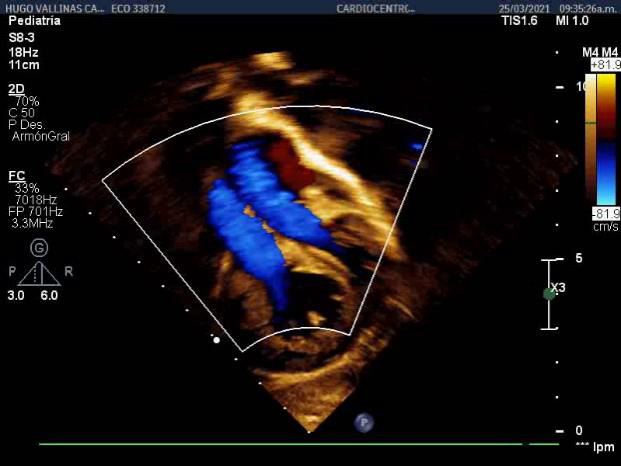

Hemoglobin: 17g / dl Hematocrit: 0.54 Leukocytes: 15x109 / l Segmented: 14% Lymphocytes: 84% Platelet count: 302 x10 9 / l Creatinine: 67 mmol / l Glycemia: 7.3mmol / l, D-dimer positive, with slight metabolic and lactic acidosis 5.1mmol / l. Chest radiograph with evidence of bilateral inflammatory-looking lesions (Figure 1). Positive Covid. During admission, invasive mechanical ventilation was not necessary, he underwent symptomatic treatment [15] for fever with dipyrone, administration of fraxiheparin (0.3 vial / 12h) for 5 days and required antibiotic therapy with Ceftriazone for a period of 10 days at doses of 150mg/ kg /day, as well as dexamethazone. Under the criteria of clinical and radiological improvement, as well as the Covid-19 infection ruled out through a virological study, the patient was discharged after 20 days, with subsequent follow-up. He was evaluated during three months after discharge by Cardiology at the William Soler Cardiocenter, serial evaluation of EKG and chest X-ray. The chest X-ray showed microatelectasis lesions and slight pulmonary edema. Echocardiogram (Figure 2) Transposition of the great vessels with closed ventricular septum, Boston type III, Aorta to the right and slightly anterior to the pulmonary. 15mm balloon atrioseptostomy with left to right shunt. Moderate tricuspid regurgitation with TAPSE = 18mm. After three months of convalescence and without evidence of sequelae from the viral infection, surgical intervention was decided. Mustard surgery was performed for definitive physiological correction, with extracorporeal circulation time of 113 minutes, aortic clamping time of 62 minutes at 23 degrees of temperature and modified hemofiltration once the extracorporeal circulation had concluded. Antimicrobial prophylaxis was used for 24 hours with Ceftriazone. There were no complications during the surgical act and in the immediate postoperative period it evolved without major difficulties. Already in the PICU, he underwent treatment with captopril, aldactone and a diuretic pump. It was possible to separate from mechanical ventilation at 24 hours of It immediately evolved without major difficulties. Already in the PICU, he underwent treatment with captopril, aldactone and a diuretic pump. It was possible to separate from mechanical ventilation at 24 hours of operated with adequate tolerance and without risk of failure at weaning, with SO2> 97%. On the third postoperative day, he presented a rhythm disorder (Figure 3) (bradycardia with complete atrioventricular block) that required placement of an external pacemaker, this complication is frequent in this type of surgery, secondary to atrial After an 8-day stay in the PICU, he was transferred to the open ward where he was admitted under treatment and monitoring for another 15 days. Hospital discharge at 23 days with treatment and monitoring by Cardiology and Cardiovascular Surgery, without complications or immediate sequelae.